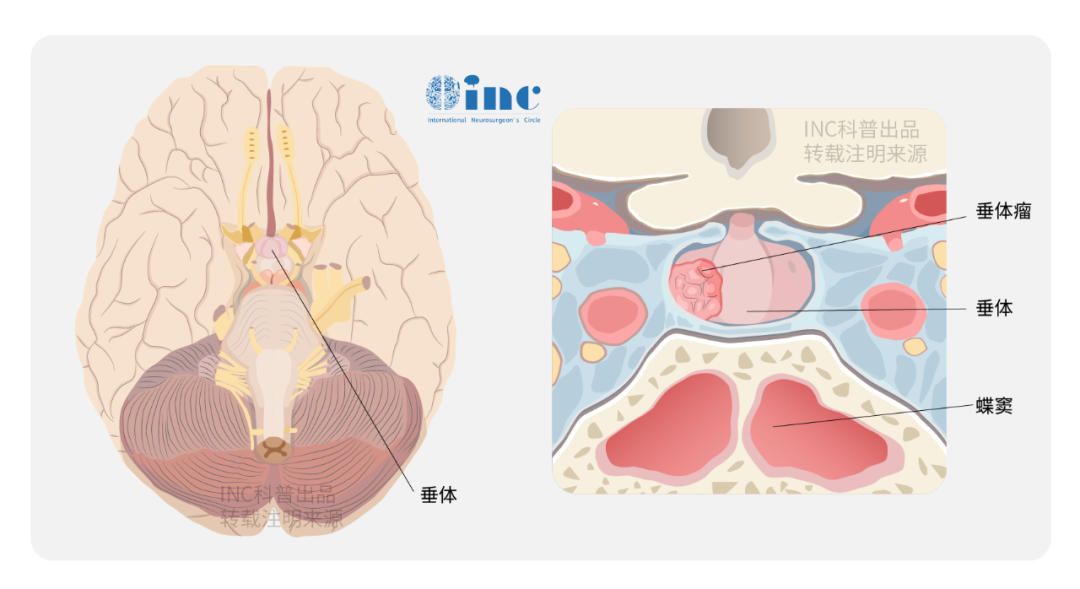

垂体为颅脑内一椭圆形小体,位于大脑底部的蝶鞍内,重约0.5-0.6克,虽小却功能强大,可以分泌多种内分泌激素,参与正常生命活动,被称为人体“内分泌腺”。垂体位于蝶骨的垂体窝(蝶鞍),腺体前下方面向蝶窦,前上方面向视交叉,侧面面向海绵窦,并通过漏斗部(垂体柄)与下丘脑相连。